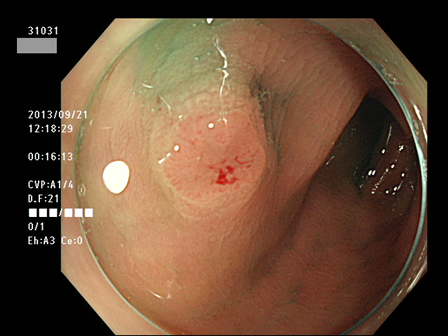

上記100名より抽出した平坦・陥凹型腺腫(=癌化の危険が高いが見落としやすい病変)の内視鏡写真